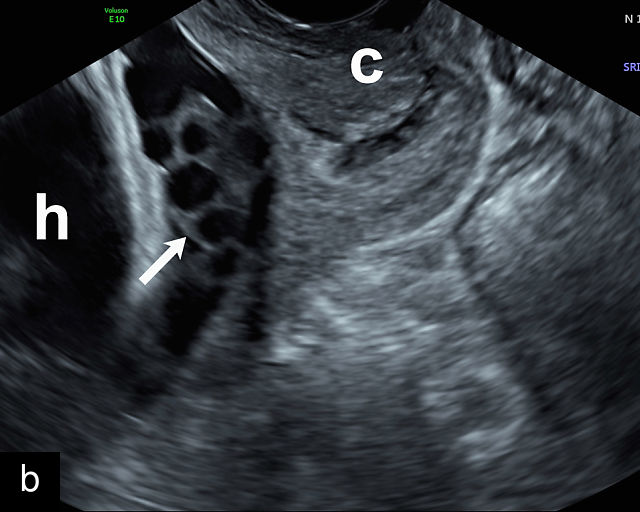

In the past, placenta previa was classified as complete, partial, marginal or low-lying.50,61 However, with advancements in ultrasound technology allowing precise assessment of the relationship between the placenta and the internal cervical os, the classification has been simplified.67 Placenta previa now refers to cases in which the placenta overlies the internal os to any degree, while low-lying placenta describes cases in which the lower placental edge lies within 2 cm of the internal os (Figure 5).51,66,67

5

Placenta previa and low-lying placenta. (a) Transabdominal grayscale ultrasound image suspicious for placenta previa. The placenta (PL) appears to overlie the internal cervical os (CX). Note the time stamp: 2:19:37. (b) Transvaginal ultrasound of the same patient taken approximately 50 minutes later. Note the time stamp: 3:10:25. The internal os and the lower placental edge are both clearly seen, and the placenta does not overlie the internal os. Because the lower placental edge is 1.93 cm from the internal os, it will likely resolve by the third trimester. (c) Transabdominal grayscale ultrasound of placenta previa. The placenta (p) covers the cervix, but the cervix, especially the internal os, cannot be visualized due to shadowing. (d) Transabdominal grayscale ultrasound of placenta previa. The placenta (p) covers the cervix (c) but shadowing obscures adequate visualization. The internal os is indicated by the arrow. (e) False-positive image of placenta previa on transabdominal grayscale ultrasound. The bladder (b) is full, pushing the anterior and posterior walls of the lower uterine segment (ls) together making it appear that the placenta (p) overlies the internal os of the cervix. In reality, the line depicted by the arrowheads is where the anterior and posterior walls of the lower segment are in proximity to each other. The cervix is much lower and is obscured by shadowing (c). (f) Transabdominal grayscale ultrasound image of placenta previa. The placenta (p) covers the cervix (c), but the cervix, especially the internal os, cannot be visualized due to shadowing. b, bladder. (g) Transvaginal grayscale ultrasound image of placenta previa. The placenta (p) completely covers the internal os (arrow) of the cervix (c). The internal os can be seen clearly. h, fetal head. (h) Transvaginal grayscale ultrasound image of posterior low-lying placenta (p). The lower placental edge is clearly seen and is 1.56 cm from the internal os (arrow) of the cervix (c). The placental edge and the internal os are clearly seen. h, fetal head. (i) Transvaginal grayscale ultrasound image of a posterior placenta previa (p). The internal cervical os is clearly seen (arrow). c, cervix. (j) Transvaginal grayscale ultrasound image of an anterior placenta previa (p). The internal cervical os is clearly seen (arrow). c, cervix; h, fetal head. (k) Transvaginal grayscale ultrasound image of a posterior placenta that was thought to be low-lying on transabdominal sonography but could not be adequately assessed. This examination clearly shows the lower edge of the placenta (p) to be 2.18 cm from the internal os (arrow) of the cervix, firmly establishing that the placenta is not low-lying and allowing the patient to undergo labor safely and deliver vaginally. c, cervix. (l) Transvaginal grayscale ultrasound image of placenta previa. The placenta (p) completely covers the internal os (arrow) of the cervix (c). The internal os can be seen clearly.

This distinction is critical in determining the mode of delivery.49,51 All patients with placenta previa persisting into late pregnancy require cesarean delivery to avoid complications such as severe bleeding.50,60,61 Studies suggest that patients with a lower placental edge located more than 1 cm from the internal os may safely attempt a vaginal delivery without a significant increase in bleeding risk.68,69,70,71

Most cases of placenta previa will be suspected prenatally by transabdominal ultrasound.49 However, this approach has several limitations and may be inaccurate.72,73,74 because the relationship between the placenta and the internal cervical os may be difficult to assess by transabdominal ultrasound.72,73,74 The bladder may be full, pushing the anterior and posterior walls of the lower uterine segment together, falsely creating the impression of a placenta previa (Figure 5e).61 There may be considerable shadowing, including by the fetal presenting part, which may limit the accuracy of transabdominal ultrasound (Figure 5d,f).75 Posterior placentas may be more difficult to assess.

Transvaginal ultrasound overcomes these limitations (Figure 5g–l).72,73,74,76 The probe is inserted into the vagina and therefore is closer to the region of interest.51,61 In addition, transvaginal transducers have higher frequencies and superior resolution compared to transabdominal transducers. Transvaginal ultrasound is safe and is not associated with increased bleeding.72,73,74,75,76 As such, transvaginal ultrasound should be the imaging modality of choice whenever there is suspicion of placenta previa.49,67,77